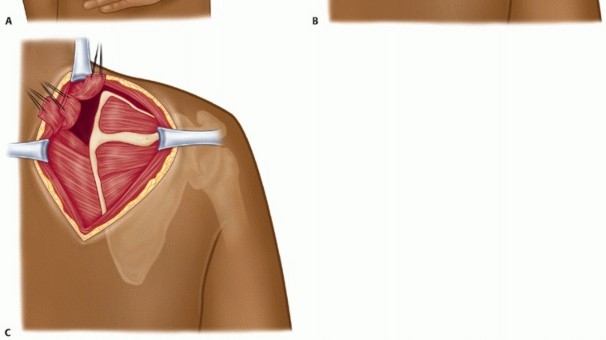

A longitudinal incision is made along the medial scapular edge (TECH FIG 1A).

Subcutaneous undermining is performed to expose the superior portion of the scapula, from the level of the scapula spine to the superomedial angle of the scapula.

Splitting and elevation of the trapezius in line with its fibers is performed at the level of the scapular spine,

and the superomedial edge of the scapula is exposed (TECH FIG 1B).

The levator scapulae and rhomboids are detached from the superior and medial edge of the scapula to expose the upper scapula border (TECH FIG 1C). Depending on the size of bony resection, the levator scapulae and upper serratus insertion are almost always detached with possible detachment of small portion of the upper part of the rhomboid minor.

Care is taken not to dissect into the rhomboids or fully detach them so as not to injure the dorsal scapular nerve, which usually is located 2 cm medial to the medial scapular edge.

A retractor is placed underneath the scapula to lift it away from the thoracic ribs.

The scapulothoracic bursa is identified against the ribs, underneath the serratus anterior muscle. A clamp is used to grasp the bursa, and sharp excision of it is performed from superior to inferior.

Subperiosteal elevation of the muscles around the superomedial border of the scapula, including the supraspinatus, infraspinatus, subscapularis, and serratus anterior muscles, is performed with the use of electrocautery to expose 1 to 2 cm of bone (TECH FIG 1D).

This exposed portion of the superomedial portion of the scapula is resected with use of an oscillating saw (TECH FIG 1E).

Once the bony resection is accomplished, drill holes are placed into the upper medial border of the scapula in order to reattach the muscles to their anatomic insertion (TECH FIG 1F) using a no. 2 nonabsorbable braided suture (TECH FIG 1G).

The skin is closed with absorbable subcuticular suture.

TECH FIG 1 • A. Patient positioned prone with hand positioned behind the back to lift the scapula off the chest wall. The surgical incision is placed over the medial border of the scapula, centered over the level of the scapula spine. B. The trapezius is split along its fibers, and the levator scapulae, the rhomboids, and the posterior surface of the scapula are exposed. C. The levator scapulae, rhomboid major, and rhomboid minor are detached from their insertion on the scapula and tagged with sutures. (continued)

TECH FIG 1 • A. Patient positioned prone with hand positioned behind the back to lift the scapula off the chest wall. The surgical incision is placed over the medial border of the scapula, centered over the level of the scapula spine. B. The trapezius is split along its fibers, and the levator scapulae, the rhomboids, and the posterior surface of the scapula are exposed. C. The levator scapulae, rhomboid major, and rhomboid minor are detached from their insertion on the scapula and tagged with sutures. (continued)

TECH FIG 1 • (continued) D,E. Resection of the superomedial border of the scapula. F. The detached muscles are reattached to the scapula through drill holes. G. The final repair of the detached levator scapulae and rhomboids. 1. ## Arthroscopic Bursectomy